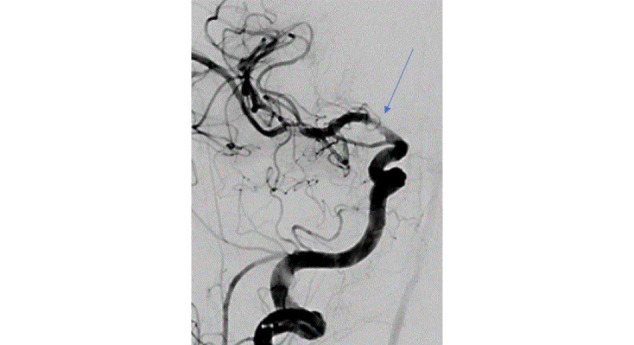

It is not uncommon for patients to suffer from both acute myocardial infarction and acute stroke during the hospitalization. According to some studies, about 12% of the elderly population initially hospitalized for acute ischemic stroke also develop type-1 acute myocardial infarction during the same hospitalization. On the other hand, about 0.9% of patients hospitalized for acute coronary syndrome develop acute stroke during the same hospitalization1. The therapeutic approach to such "overlapping" patients is challenging, especially if we also take into account a high risk of bleeding and/or active bleeding. Therefore, interdisciplinary collaboration between cardiology, neurology and interventional neuroradiology is of key importance. Timely intervention and adequate concomitant drug therapy (primarily antiplatelet and anticoagulant therapy) determine treatment outcomes and long-term results. In our recent clinical work, we treated a patient with a series of acute cardiac and cerebral incidents presenting multiple therapeutic dilemmas, who ultimately had an unfavourable neurological outcome.